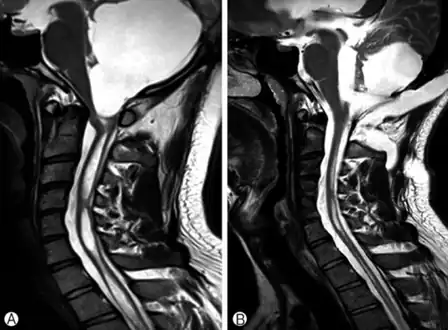

Physicians now use magnetic resonance imaging (MRI) to diagnose syringomyelia. The MRI radiographer takes images of body anatomy, such as the brain and spinal cord, in vivid detail. This test will show the syrinx in the spine or any other conditions, such as the presence of a tumor. MRI is safe, painless, and informative and has greatly improved the diagnosis of syringomyelia.[14][15][16][17][18][19][20][21][22][23][24][25]

The first major form relates to an abnormality of the brain called an Arnold–Chiari malformation or Chiari malformation. This is the most common cause of syringomyelia, where the anatomic abnormality, which may be due to a small posterior fossa, causes the lower part of the cerebellum to protrude from its normal location in the back of the head into the cervical or neck portion of the spinal canal. A syrinx may then develop in the cervical region of the spinal cord. Here, symptoms usually begin between the ages of 25 and 40 and may worsen with straining, called a valsalva maneuver, or any activity that causes cerebrospinal fluid pressure to fluctuate suddenly. Some patients, however, may have long periods of stability. Some patients with this form of the disorder also have hydrocephalus, in which cerebrospinal fluid accumulates in the skull, or a condition called arachnoiditis, in which a covering of the spinal cord—the arachnoid membrane—is inflamed.[11] Some cases of syringomyelia are familial, although this is rare.[12]